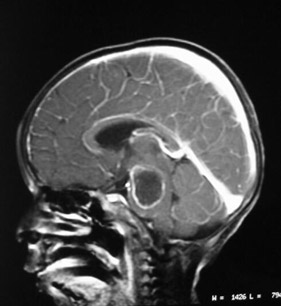

El análisis rápido de tomografías cerebrales puede salvar vidas.

El análisis rápido de tomografías cerebrales puede salvar vidas.

(Gentileza)